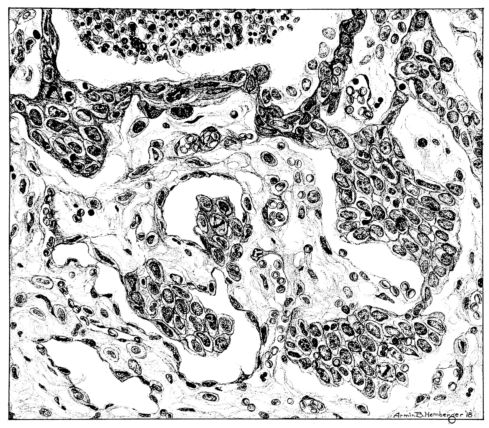

FIG. IV. AUTOPSY NO. 205. CONGESTION AND EDEMA OF THE SUBMUCOSA AND REGENERATION OF THE TRACHEAL EPITHELIUM.

The changes are less marked, perhaps, in the trachea than in its finer ramifications. The mucosa is constantly more or less destroyed and large areas, usually focal, are entirely devoid of their epithelial covering. This is replaced by a sparse exudate, composed largely of red blood cells, mucus, a small amount of fibrin, and nuclear fragments (Fig. II). It may dip into the submucosa for a short distance, but usually these indentures are associated with the ducts of the mucous glands into which the inflammatory reaction extends. A more striking feature than the exudate, however, is the edema and the congestion of the submucosa. The loose areolar tissue of the submucosa is spread widely apart, and throughout it distended blood vessels are very conspicuous. Occasionally such a vessel is broken and actual hemorrhage appears in the submucosa. Occasionally, too, the inflammation extends down the duct to the mucous gland itself, and here, also, aplastic inflammatory reaction is evident, inasmuch as the acini now stain intensely red with the cells undifferentiated from each other and specked here and there by broken remains of the dead nuclei (Fig. III). After the disease has continued for a short period, even at the end of five or six days, some regeneration of the epithelial lining may be seen (3) (Fig. IV). But despite this, the acute picture persists, and there goes on, side by side, an attempted repair characterized by epithelial regeneration and the same evidence of acute change. Since the lesion is essentially a superficial one, scars or contractures of any extent are not encountered in the trachea, even in examples of the disease that have ended fatally only after many weeks.[4]